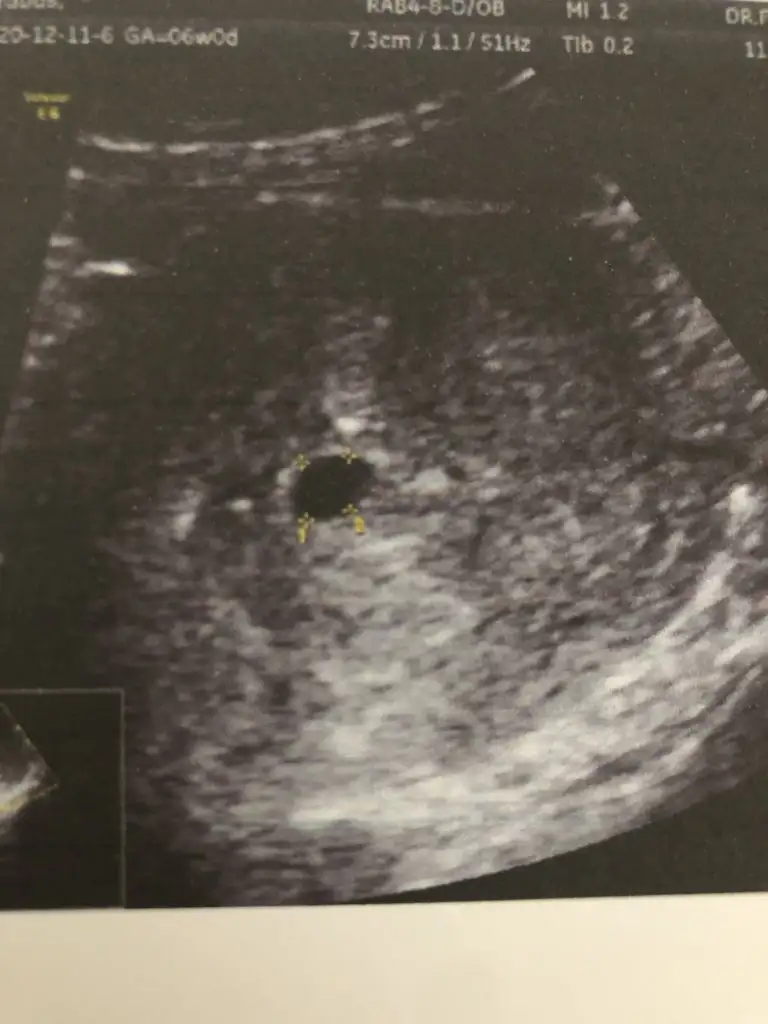

baya net çıkmış kese vajinal usg mı yaptı doktorun

Yok kuzum üstten baktı doktorum geç döllenme olmuş annesi 2 haftaya kalbini duyarız dedi adete göre 6 haftalığım tam ultrasona ve hcg değerine göre 5 haftalığız

Kizlar cok sükür simdi ciktim. Tam 6 haftalik kalp atisinida duyduk .doktor kanama alani yok dedi. Ama benim lekeler nerden geliyor bilmiyorum. Doktor riskli gebelik 10.haftaya kadar kimseye söyleme dedi. Darisi bütün arkadaslara insallah

anladım canım kese boyutunu söyledi mi doktorun